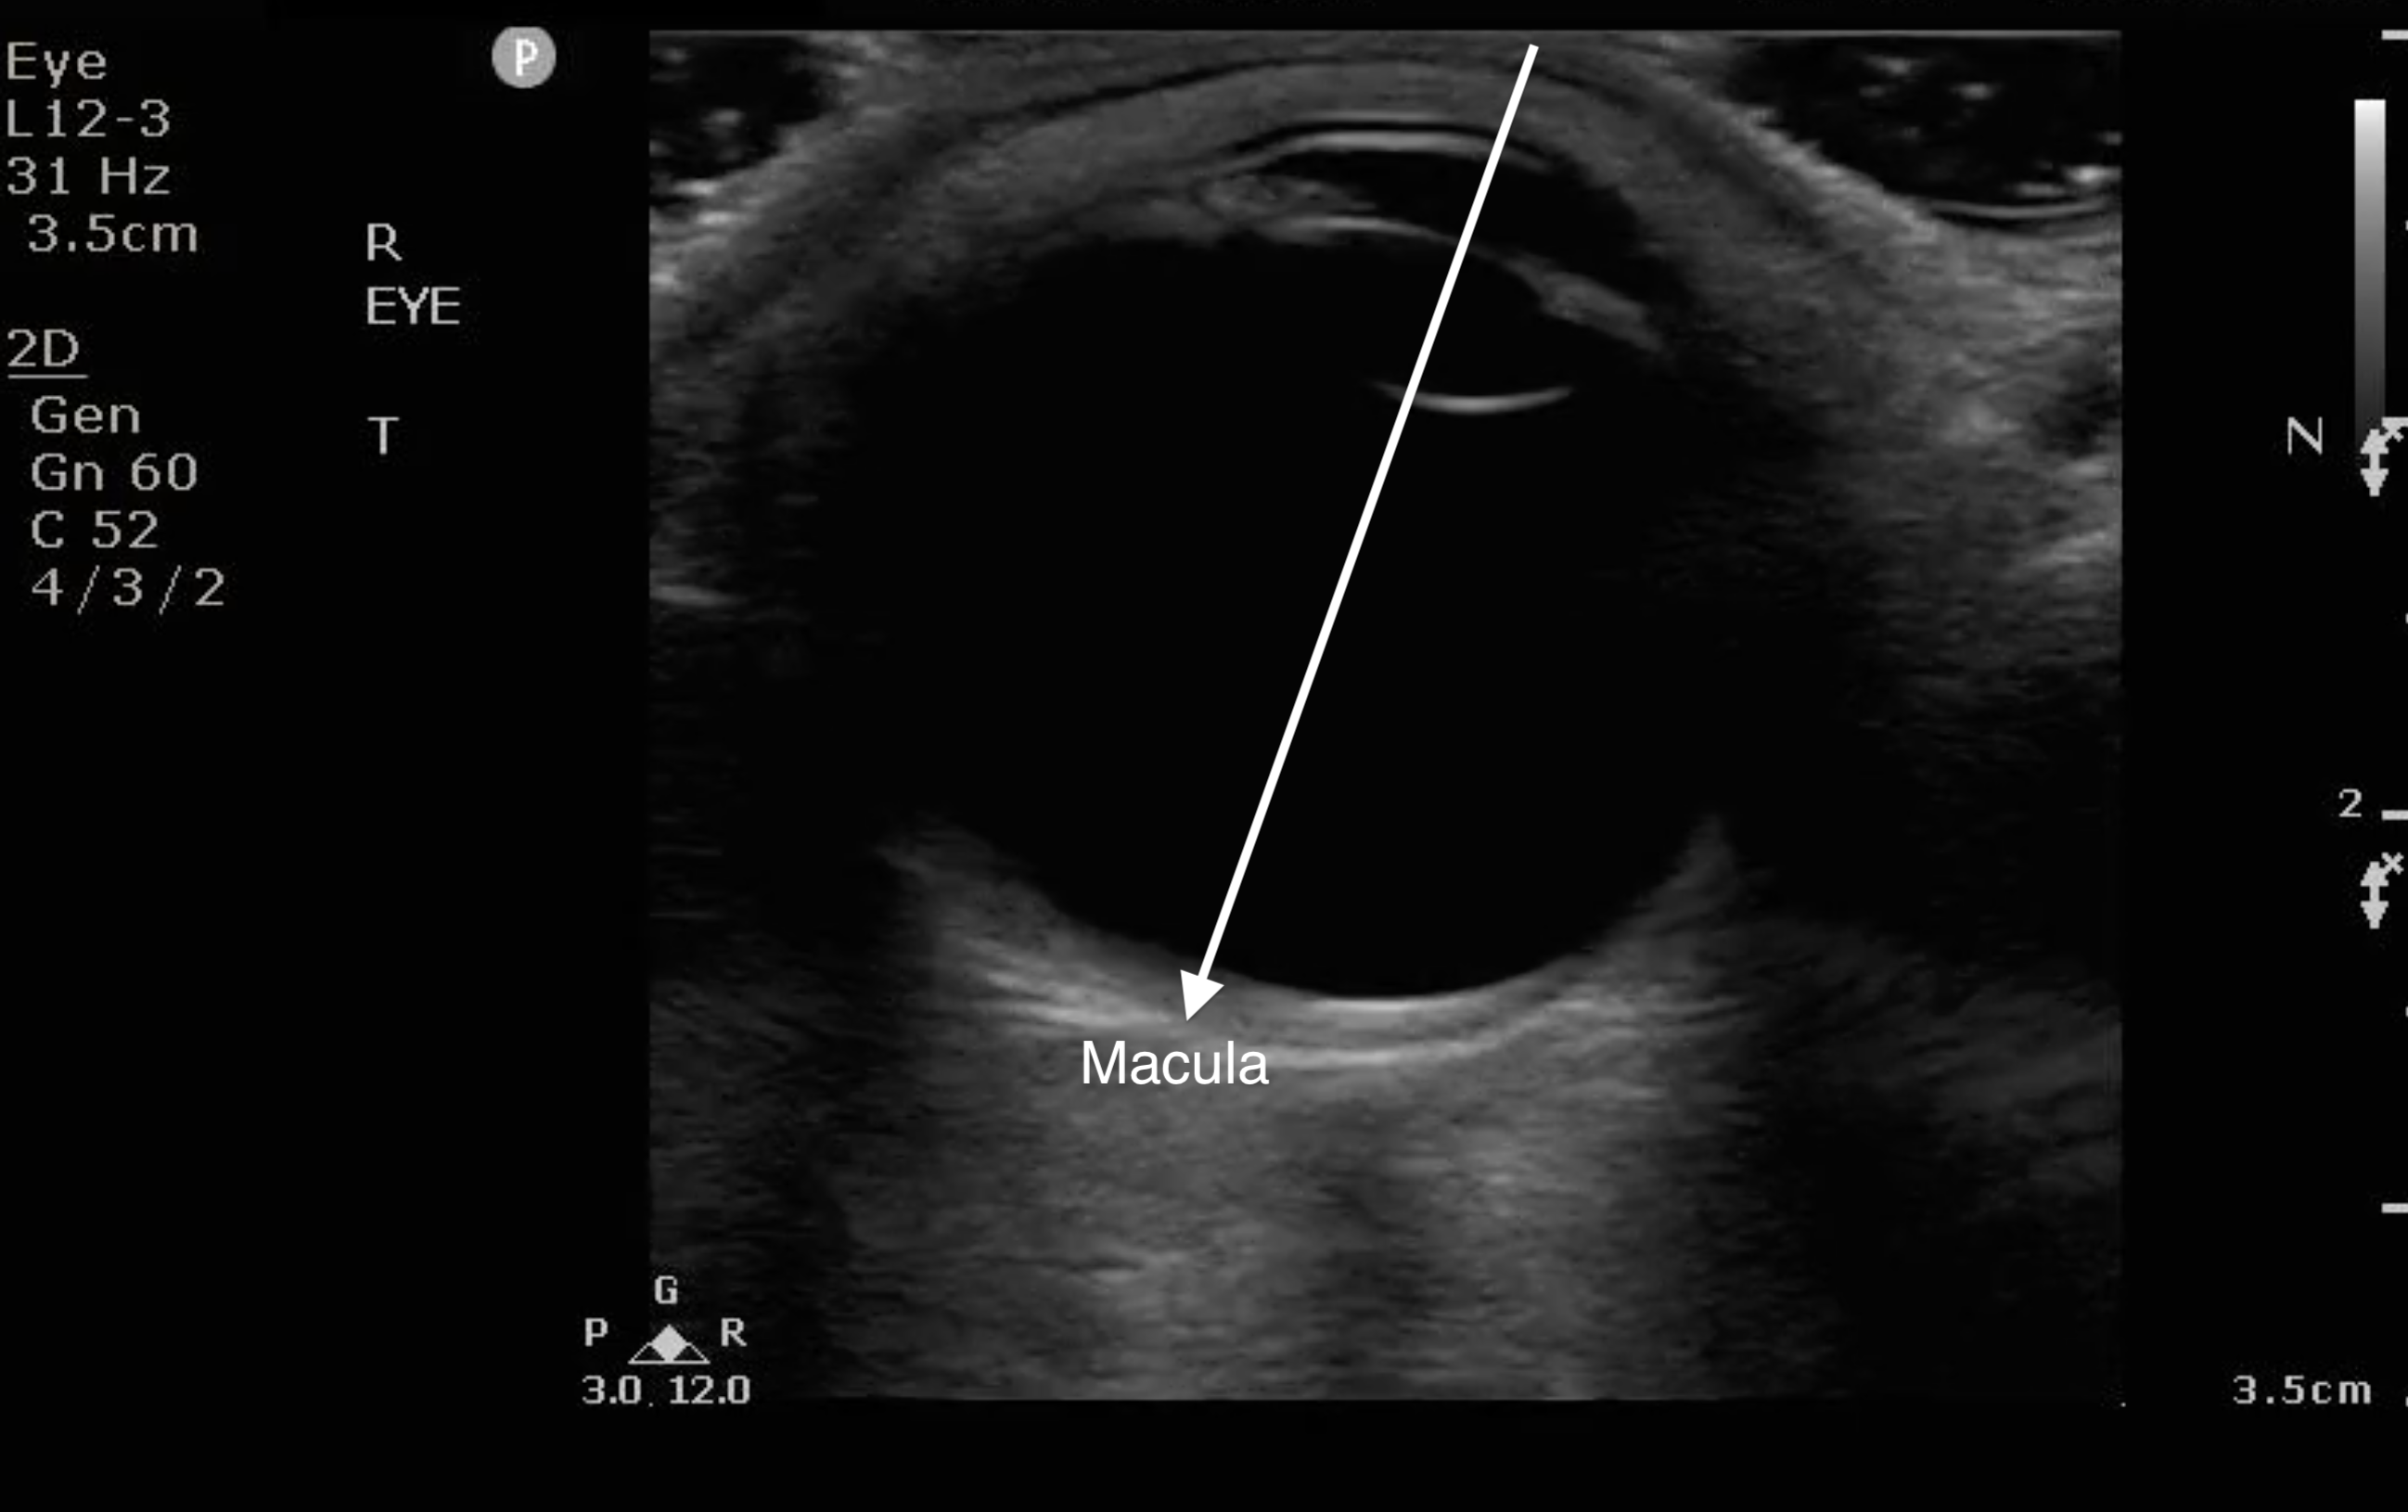

- The macula is temporal to the optic nerve. It cannot be visualized sonographically though location can be approximated by the location of lens (see Fig. 8). If the RD extends temporally from the base of the optic nerve, it can be assumed that it has come off of the macula (“mac off retinal detachment”).

- Figure 8. When the anterior chamber is lined up with the lens, draw a line to bisect the globe to the back on the temporal side. That is where the macula is located.

- RD with the retina still over the macula is an ocular emergency warranting an emergent consultation to ophthalmology in order to take measures to prevent the retina from coming off of the macula.

- RD with the retina off the macula requires an urgent follow-up with ophthalmology.